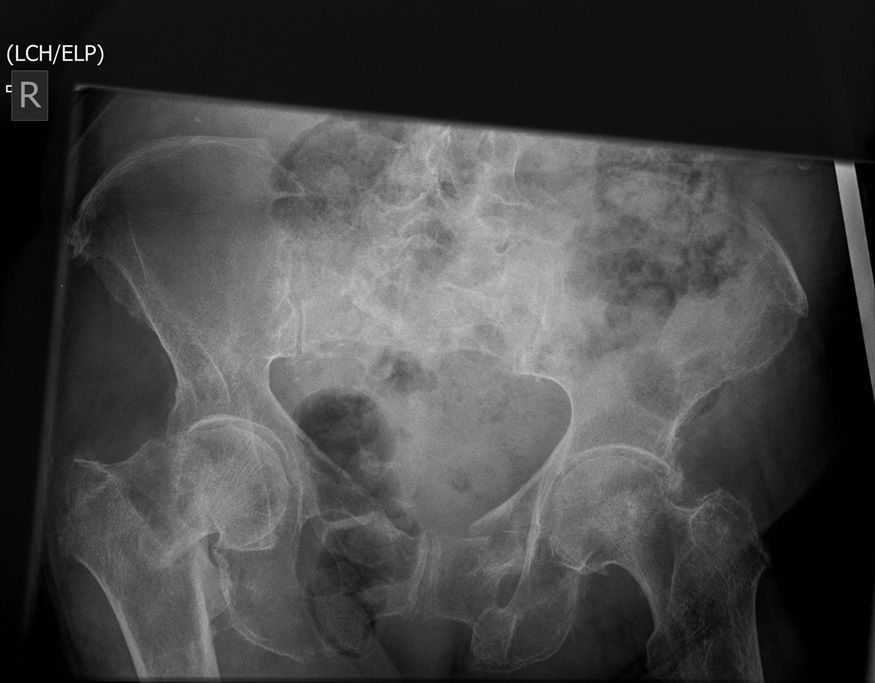

I was hoping you would partake in a study we are doing. We want to establish if there is any bias when deciding an operation based on the radiograph. We understand that the NICE guidelines state that the patient management for hip surgery should not be based on the radiographic findings; rather it should be based on defined criteria. However with that aside what we are requesting is that you look at the film + decide what operation either THR or Hemiarthroplasty. Click the dot + select answer.

Question 1

Question

Which operation would you chose?

Answer

• THR

• Hemiarthroplasty